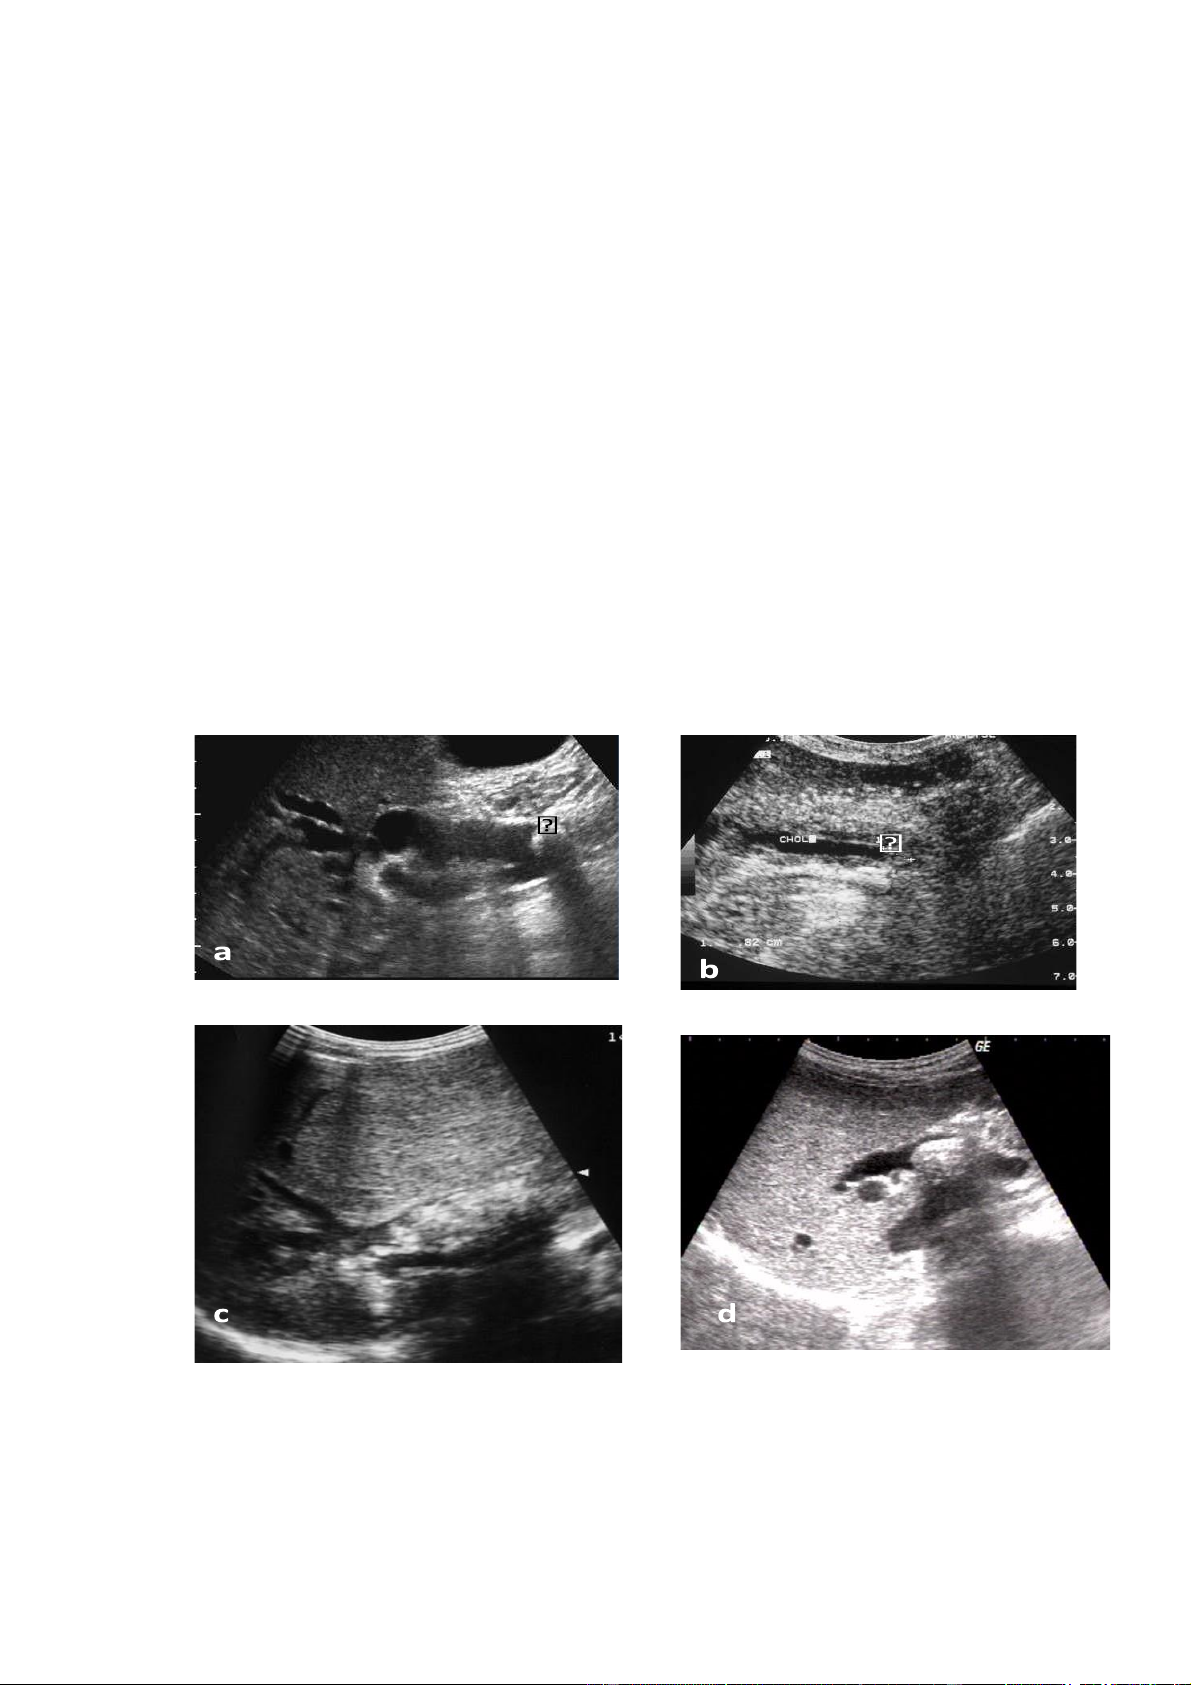

bHình. 6,1.3. sỏi túi mật a. Nhiều sỏi túi mật b.

sỏi phểu túi mật + viêm túi mật cấp c.

sỏi kẹt phểu và túi mật chất đầy bùn mât

Hình 6.1.4 . Viêm túi mật cấp

a.Viêm túi mật cấp thể nhẹ: thành

túi mật dày, dịch quanh túi mật, sỏi túi mật.

b, c. Viêm túi mật cấp hoại tử:

thành túi mật dày, gián đoạn, áp xe quanh túi mật

Hình 6.1.5 . Viêm túi mật mạn

a. Viêm teo túi mật: túi mật teo nhỏ, thành

dày, chất đầy sỏi, không còn dịch mật

b. Viêm túi mật mạn: túi mật vẫn còn dịch

mật, có sỏi, thành dày tăng âm và có

lắng đọng cholesterole trong thành.

c. Thành túi mật vôi hoá: hình trên phim

chụp khu trú vùng gan mật

d. Thành túi mật vôi hoá: hình siêu âm